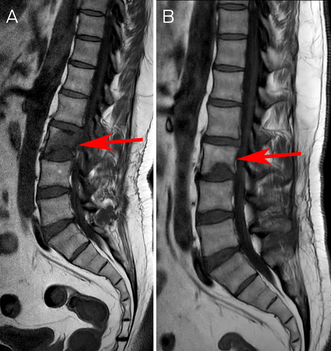

Cryptococcal vertebral osteomyelitis was diagnosed based on characteristic histology and positive serology. Biopsy for culture was not re‐attempted due to patient preference. Liposomal amphotericin B and 5‐fluorocytosine four‐week induction was commenced. His back pain improved, and he was changed to fluconazole consolidation and then maintenance therapy. Currently, he has completed 13 of 18 planned months of therapy with radiological improvement of the osteomyelitis (Box 3). The right lower lobe opacities have resolved; the pulmonary nodules and lymphadenopathy are unchanged.

Box 3 – (A) Sagittal section T1‐weighted turbo‐spin‐echo (TSE) magnetic resonance imaging (MRI) scan showing L2 osteomyelitis and discitis two months after treatment commencement (June 2022). (B) Sagittal section T1‐weighted TSE MRI scan showing radiological improvement after nine months of treatment (January 2023)